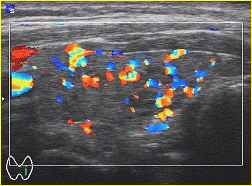

На рисунке 3 представлена ультразвуковая картина

узла ЩЖ с применением допллерографии. Усиление кровотока по периферии узла.

Рисунок 3. УЗ-картина узлового зоба